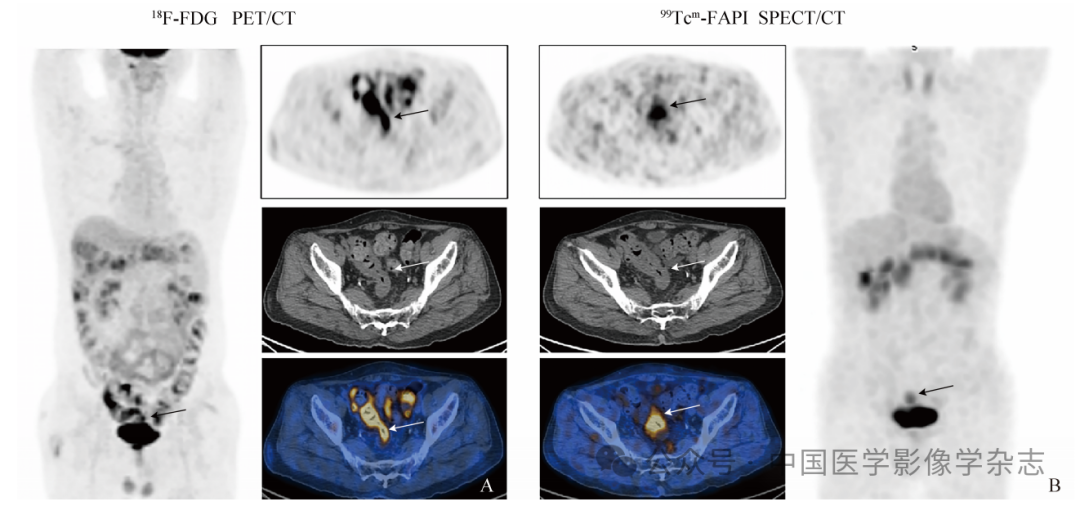

34例患者中,肿瘤原发灶、腹膜种植转移灶和肝转移灶对99Tcm-FAPI的摄取明显高于对18F-FDG的摄取,差异有统计学意义(Z=-2.389、-2.497、-0.106,P均<0.05);转移淋巴结对99Tcm-FAPI和18F-FDG摄取差异无统计学意义(Z=-0.699,P=0.485),见表1、图1。

图1  男,59岁,肠镜活检确诊结肠癌,结肠癌原发灶在18F-FDG PET/CT和99Tcm-FAPI  SPECT/CT显像的对比图(箭示病灶)。A. 18F-FDG PET/CT最大密度投影及横断位图像示肠道走行区18F-FDG生理性摄取,影响结肠癌病灶判读;B. 99Tcm-FAPI  SPECT/CT中肠道走行区无生理性99Tcm-FAPI 摄取,结肠癌病灶显示清晰